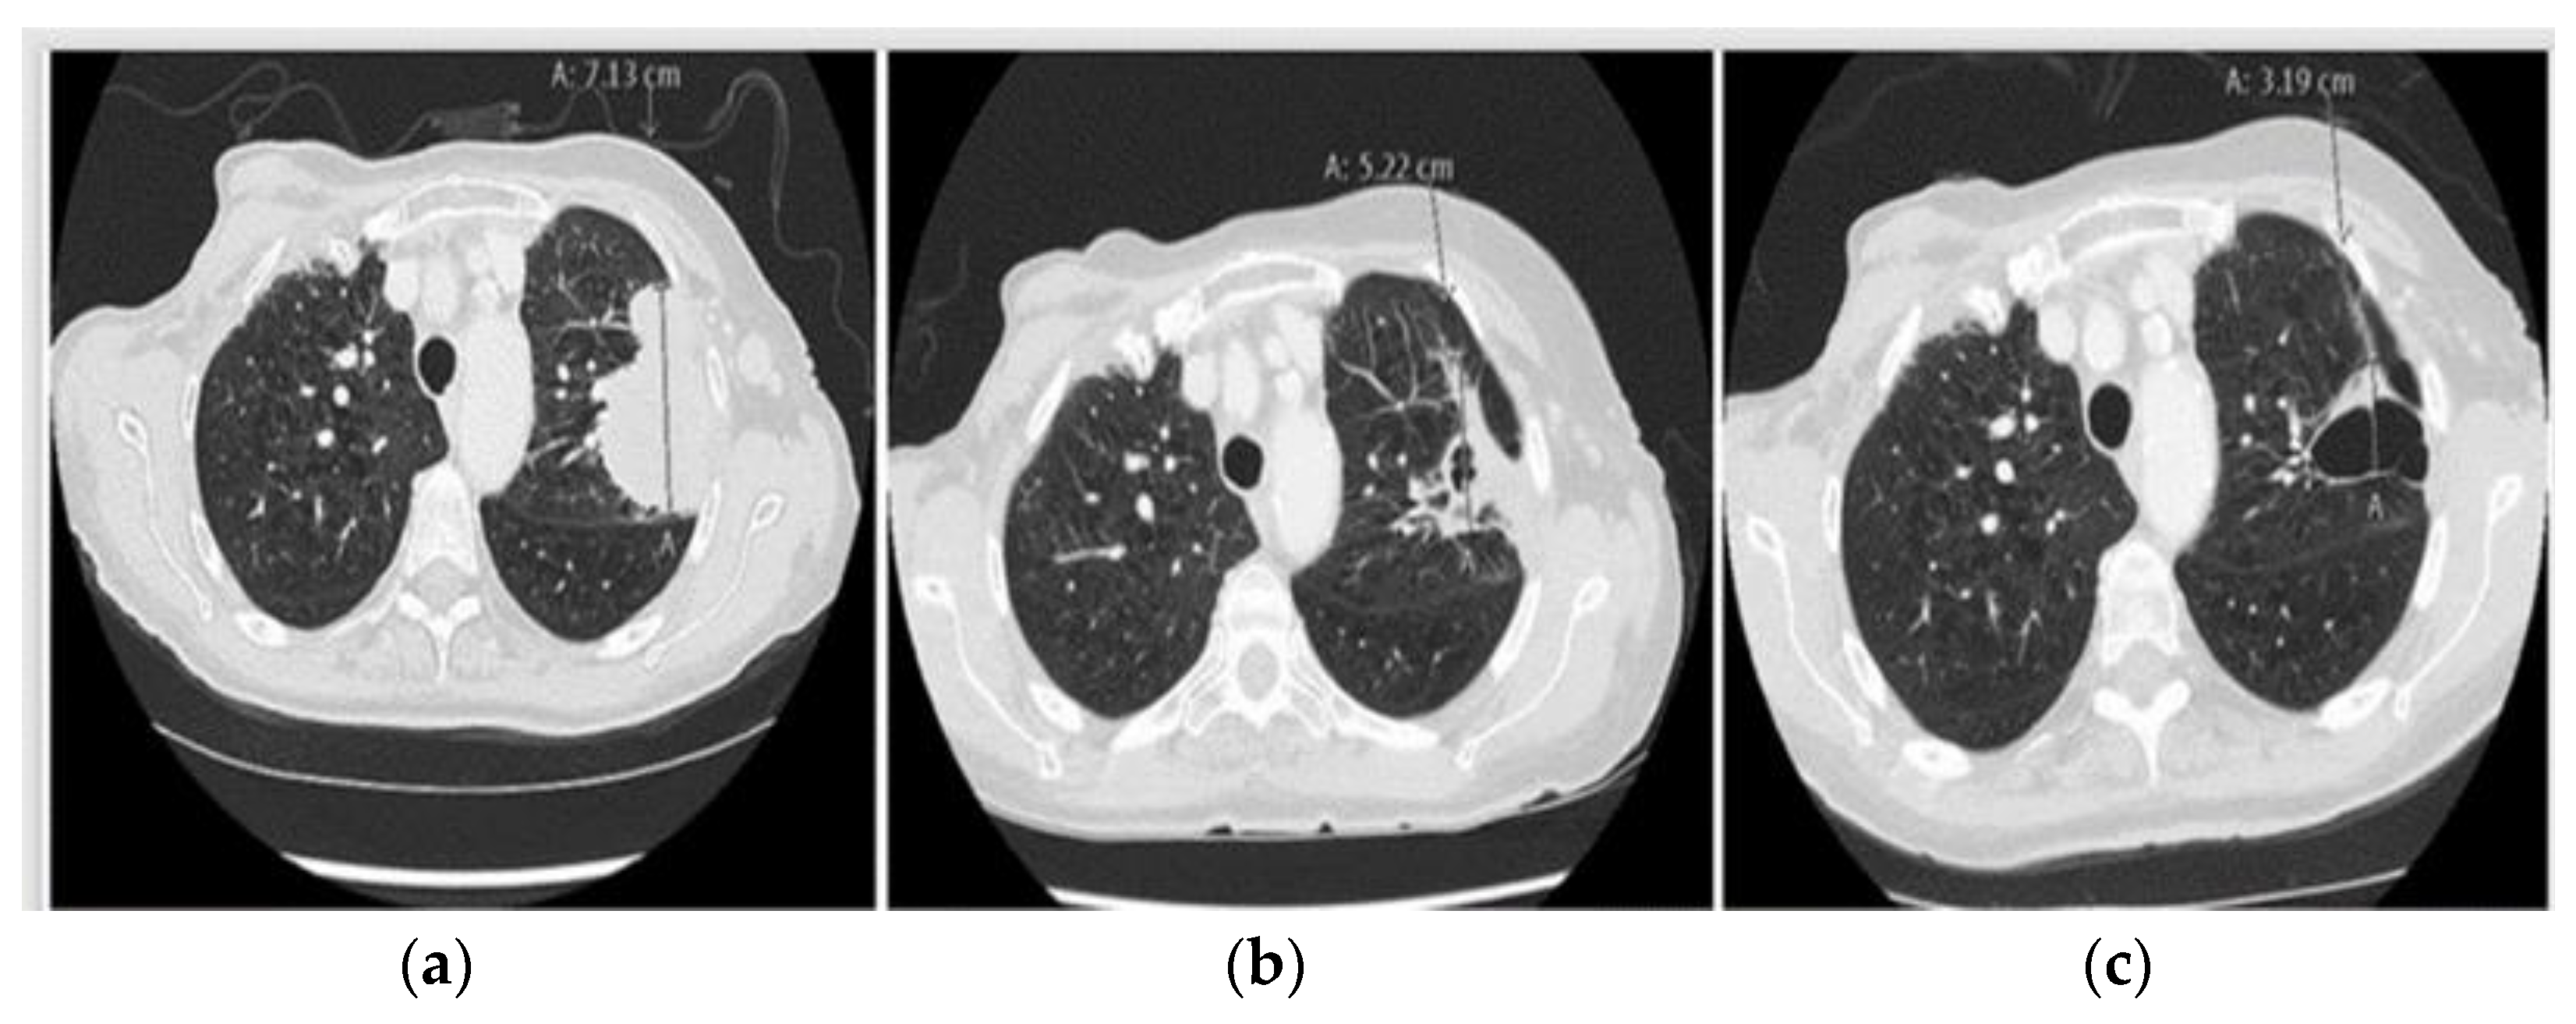

2.2. Case 2: Transient Efficacy of Crizotinib for Acquired MET Dysregulations Accompanied by Squamous Cell Transformation

2.3. Case 3: Crizotinib Rescues the Third Progression on Osimertinib Associated with Complex Resistance Mechanisms

2.4. Case 4: Durable Response of Metastatic EGFRm+ NSCLC to Fourth Line Gefitinib Rechallenge Combined with Crizotinib Because of Acquired High-Level MET Amplification